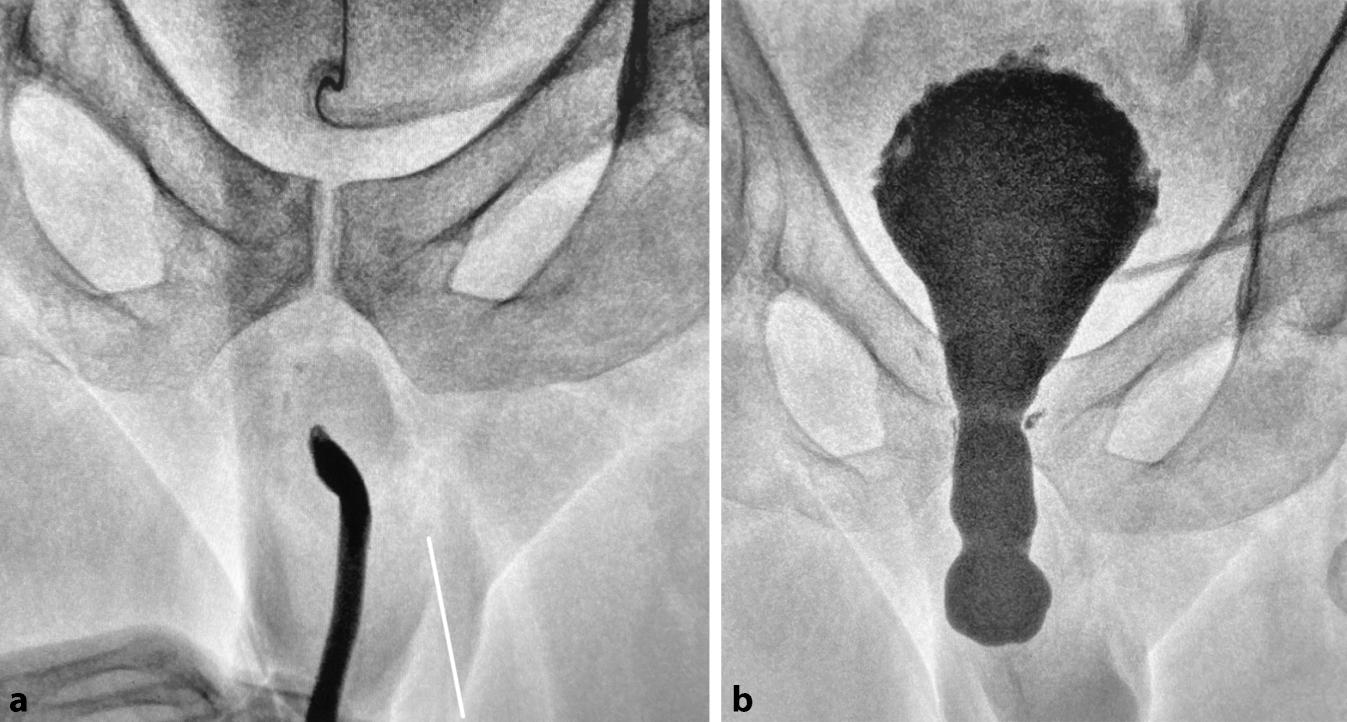

Die körperliche Untersuchung bedeutet die Exploration und Palpation des äußeren Genitales (Vorhaut, Lokalisation und Beschaffenheit des Meatus, Fisteln, Vernarbungen, Lichen sclerosus). Die Uroflowmetrie kann als einfache und kostengünstige Untersuchungsmethode zur Objektivierung einer Harnblasenentleerungsstörung eingesetzt werden und ist insbesondere als Verlaufskontrolle und zur Erkennung von Rezidiven nach Operationen hilfreich [2, 13]. Die retrograde Urethrographie (RUG) in Kombination mit einer Miktionszystourethrographie (MZU) sind in der klinischen Routine das diagnostische Mittel der Wahl, um Lokalisation, Länge und Ausmaß der Striktur abschätzen zu können (Abb. 1). Eine suffiziente präoperative Evaluation ist überwiegend durch die Kombination dieser beiden Urethrographien (kombiniertes RUG/MZU) möglich. Eine Urethrozystoskopie (retrograd/antegrad) ist fakultativ und nur begrenzt aussagekräftig, da die Striktur meist nicht atraumatisch überwindbar ist und somit die Harnröhre nur bis zur Striktur gespiegelt und eingesehen werden kann. Der dynamische Ultraschall der Harnröhre konnte sich in der klinischen Routine bisher nicht etablieren, obwohl hier Lokalisation und Länge und v. a. das Ausmaß der Spongiofibrose besser bestimmt werden können [14].

Abb. 1

Retrograde (a) und antegrade (b) Urethrographie einer posttraumatischen bulbären Harnröhrenstriktur